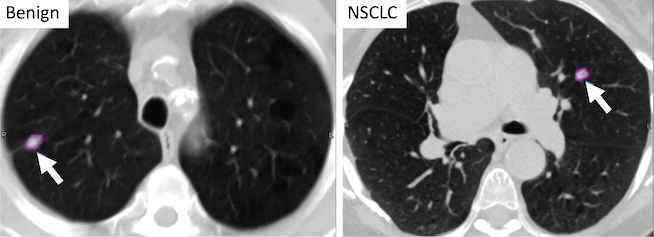

Some nodules are straightforward to interpret. A heavily calcified lung nodule that stays stable over time is usually benign and may suggest an old healed infection. A growing nodule with spiculated edges may be more concerning for lung cancer. An indeterminate lung nodule falls between these two easily categorizable extremes and needs a structured follow-up plan.

Image Source: Fred Hutch Cancer Center